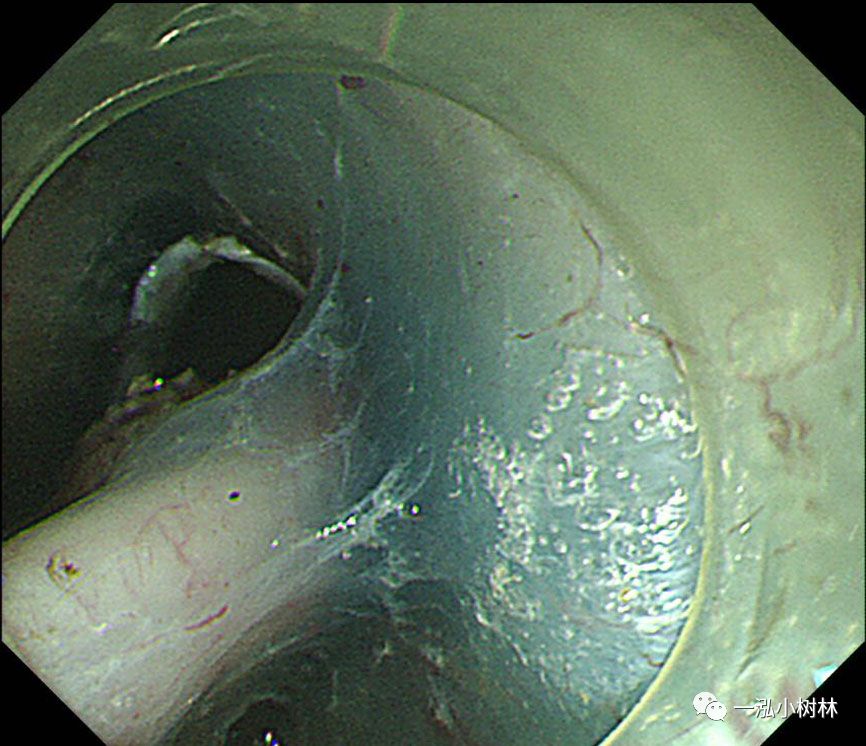

图1 白光内镜:食管中段后壁可见50mmIIb病变。